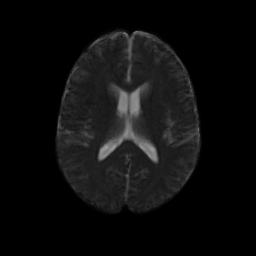

Our methodology for population analysis of DT-MRI is based on unbiased non-rigid registration of a population to a common coordinate system. The registration jointly produces an average DTI atlas, which is unbiased with respect to the choice of a template image, along with diffeomorphic correspondence between each image. The registration image match metric uses a feature detector for thin fiber structures of white matter, and interpolation and averaging of diffusion tensors use the Riemannian symmetric space framework. The anatomically significant correspondence provides a basis for comparison of tensor features and fiber tract geometry in clinical studies.

Our registration procedure is based on a scalar feature image which is sensitive to sheet like structures. We have observed that the major fiber bundles of interest occur as sheet or tube like manifolds in the FA image of the brain. As a feature image we use the maximum eigenvalue of the hessian of the FA image. Images are initially aligned using an affine registration and then deformed to a common coordinate system using the unbiased atlas-building procedure of Joshi et al. [1]. The deformation fields produced by the registration process are applied to the tensors fields using appropriate methods for reorienting and interpolating tensors. The transformed images are averaged in the atlas space to produce a DTI atlas.

An initial test was performed by using the procedure on a set of images of healthy subject at age one year. The results of the tensor averaging are shown on the right. Tractography was also performed on the mean atlas image as shown.